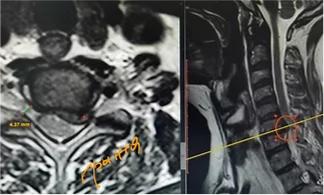

На МРТ показана грыжа, сдавливающая корешок в корешковом канале. На компьютерной томографии показан остеофит, который может создавать дополнительную компрессию спинального корешка.